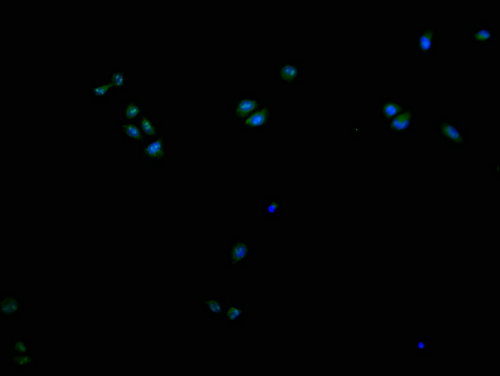

Immunofluorescence staining of Hela cells with CSB-PA621969LA11HU at 1:200, counter-stained with DAPI. The cells were fixed in 4% formaldehyde and blocked in 10% normal Goat Serum. The cells were then incubated with the antibody overnight at 4°C. The secondary antibody was Alexa Fluor 488-congugated AffiniPure Goat Anti-Rabbit IgG(H+L).

Application Recommended Dilution IF 1:100-1:500 -